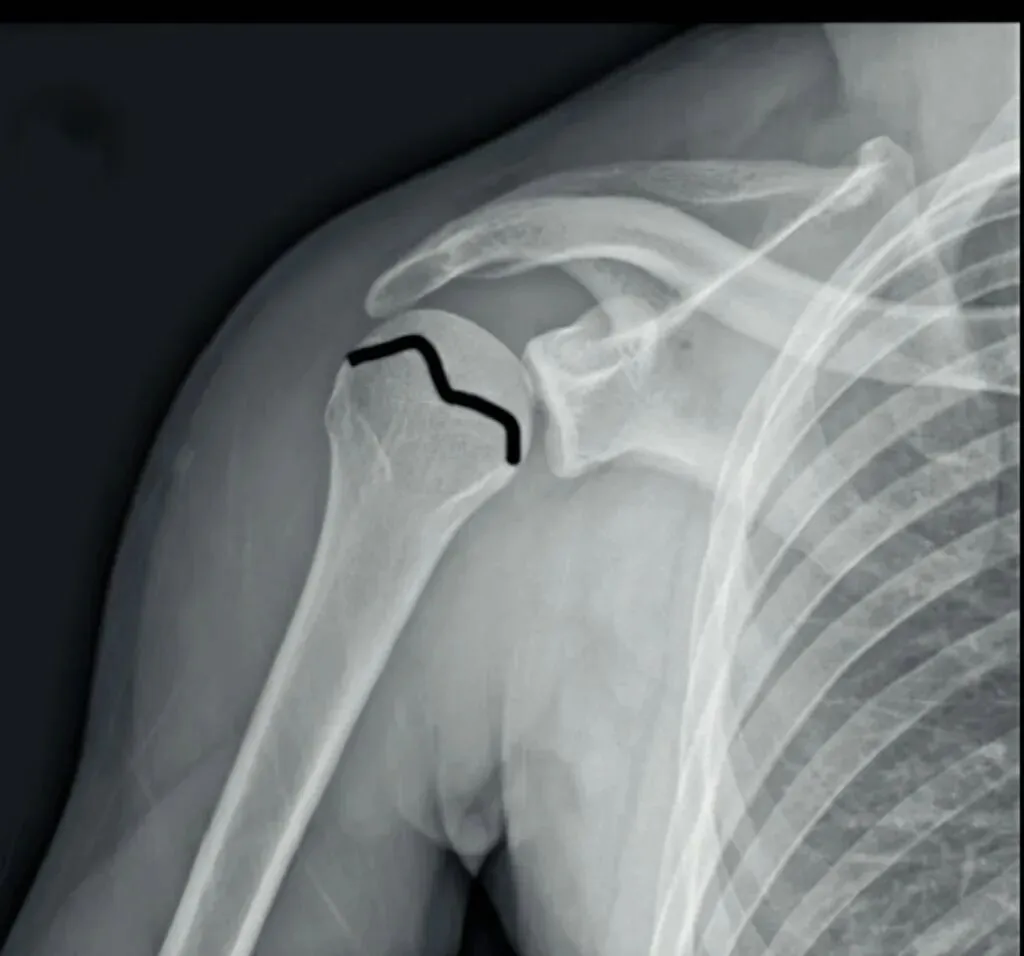

其次,我们要注意外伤患者不仅有肩关节脱位,有时还会伴随骨折出现。有一个很典型的影像学表现就是槽线征,当肱骨头撞击关节盂后缘,骨质形成压缩性骨折,表现为肱骨头内侧骨皮质与反Hill-Sachs骨折块形成的近乎平行线,称槽线征。

槽线征的识别对判断肱骨头内侧压缩性骨折至关重要。我们可以在肩关节的X线或者CT检查中清晰看到后脱位的肱骨头向关节窝的后方移位,同时也可显示肱骨头内侧受撞击形成的压缩性骨折(反Hill-Sachs骨折)。

需要注意出现槽线征时,盂肱关节间隙有时候狭窄,也有时候是增宽的,这也是在只有肩关节正位X线检查中比较容易出现漏诊的地方。